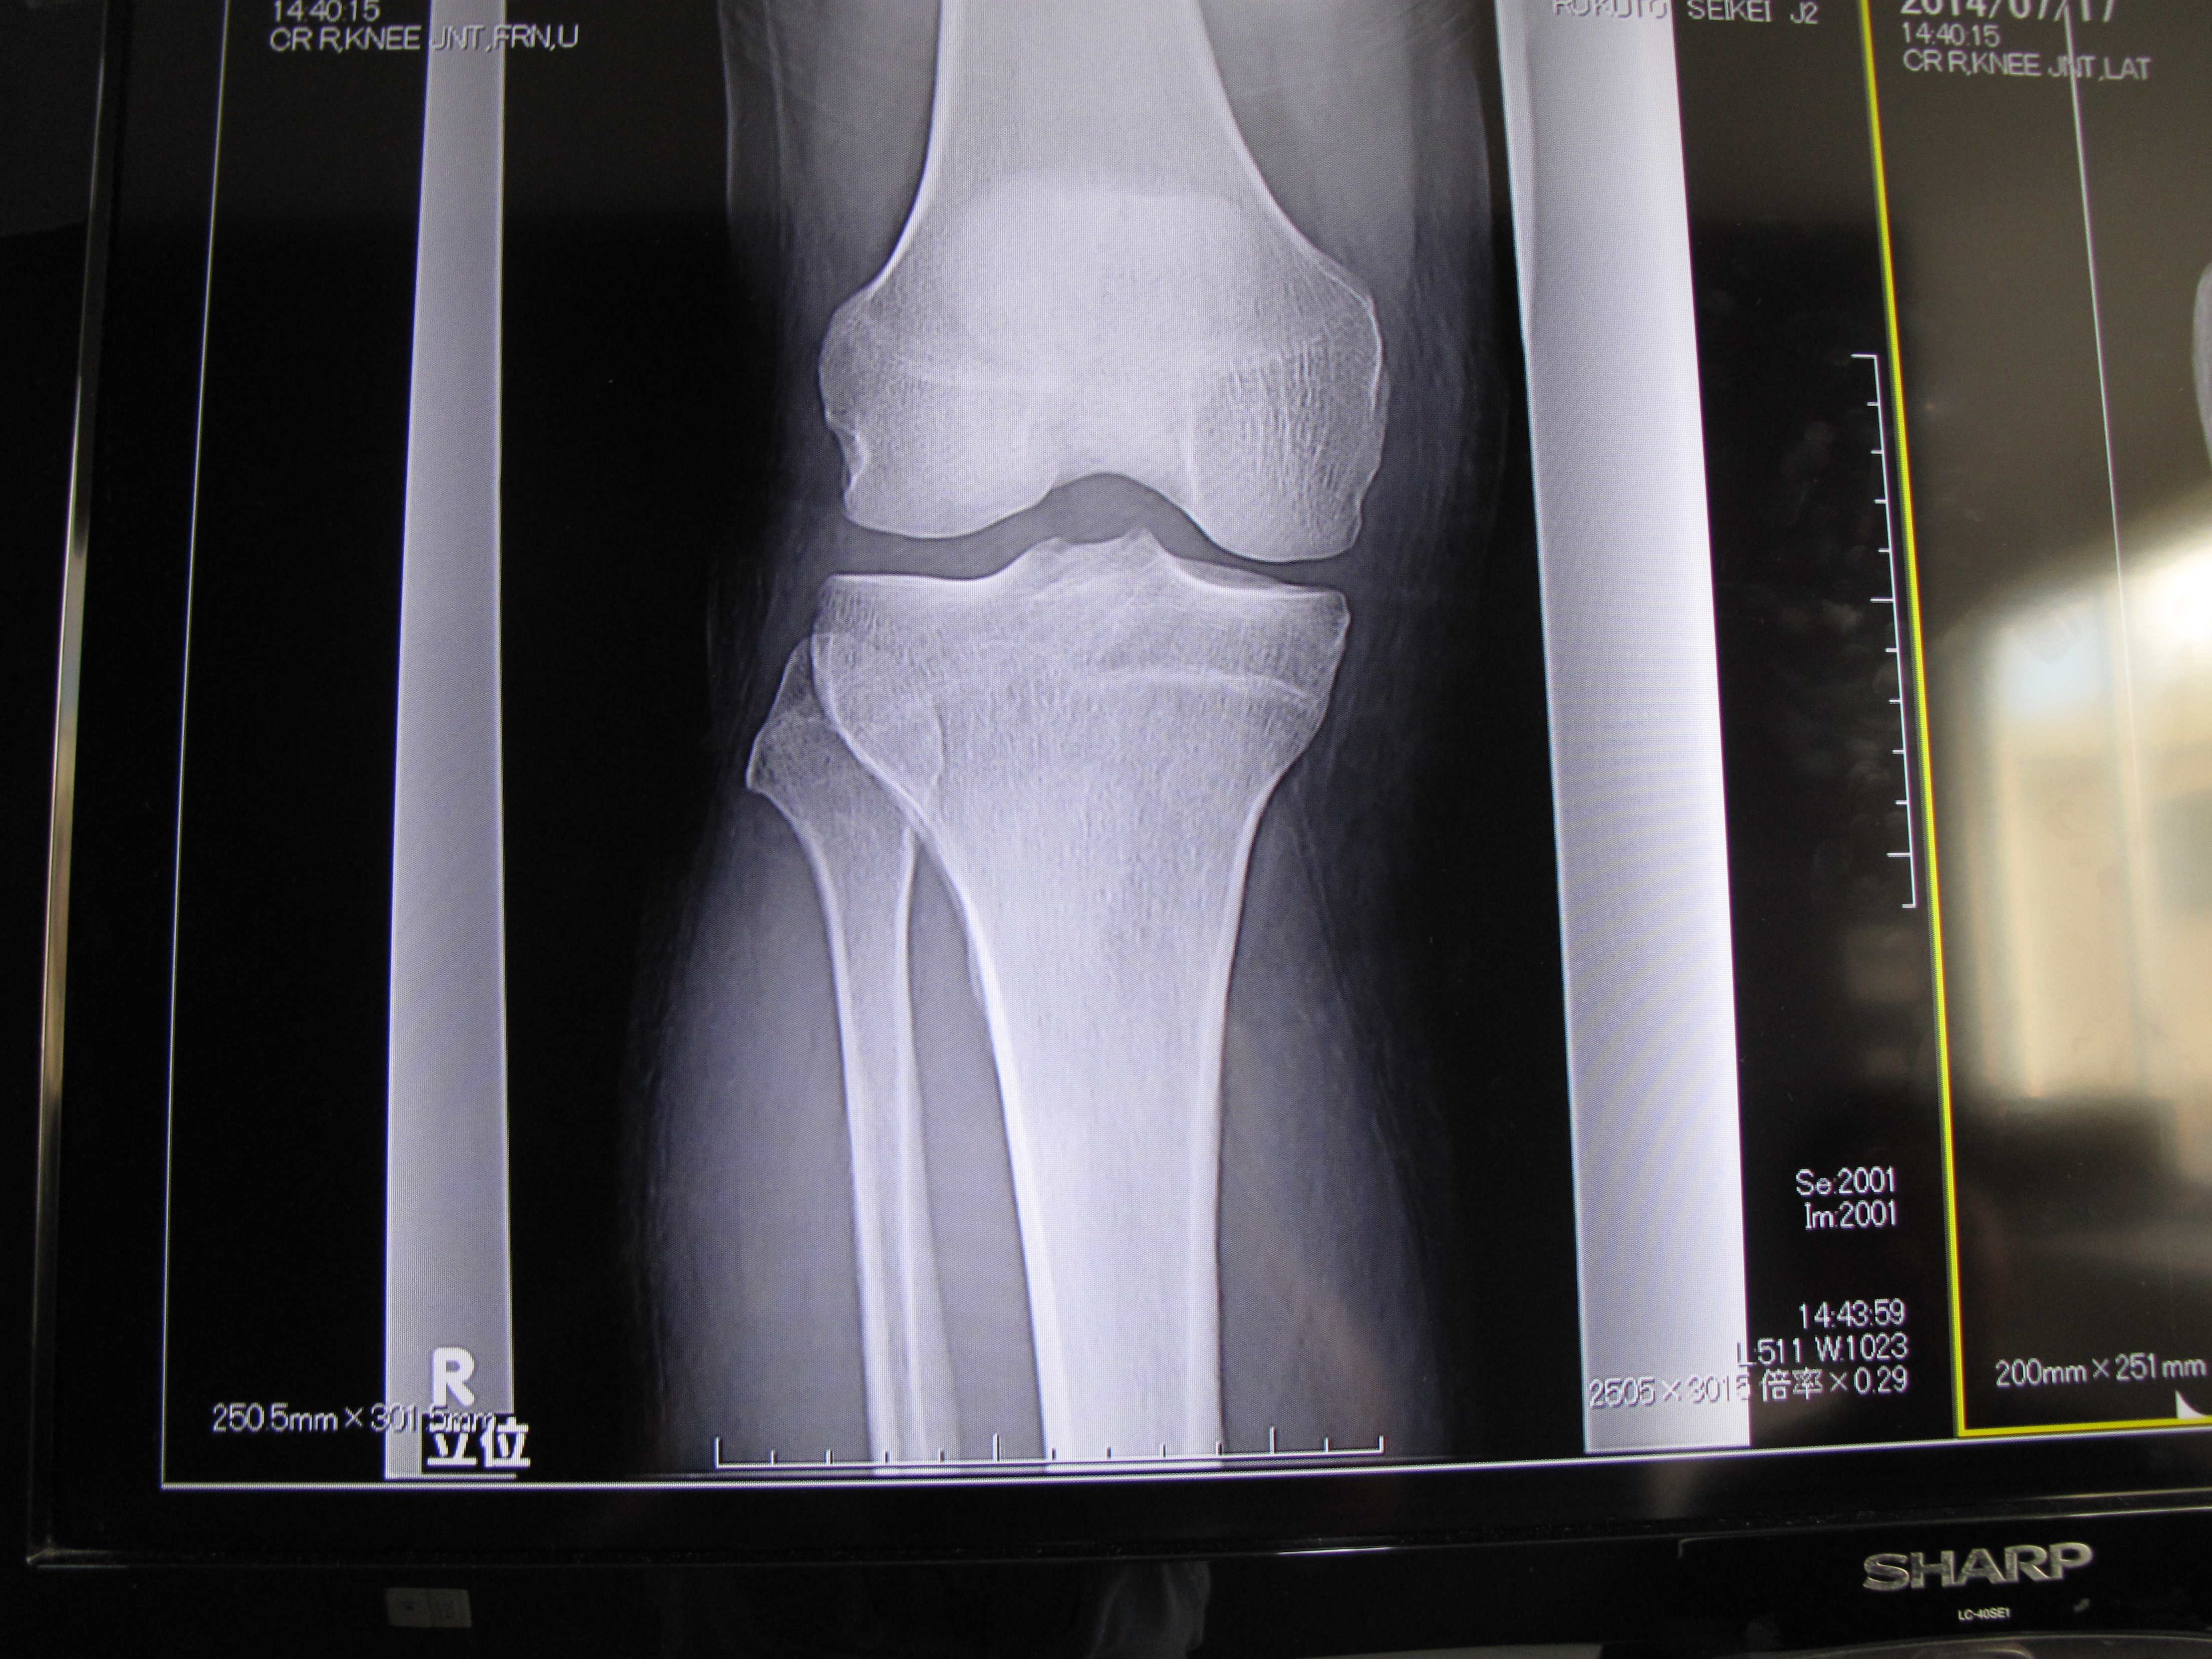

What fun! A visit to a Japanese medical clinic is always worthwhile, if not for the treatment, then for the experience. I do not mean to say that the treatment is bad – on the contrary – but more that each visit is an adventure. First, I have an X-ray.